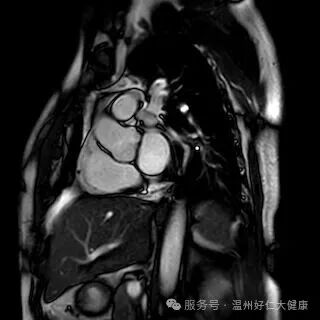

针对心脑血管早筛的核心需求,我院全力推进冠脉磁共振检查技术普及,凭借无创、无辐射、不打造影剂的硬核优势,攻克传统筛查的痛点,成为不同人群冠脉血管筛查的优选方案,让早期血管病变无所遁形:无创安全,适配全人群:全程无需插管、不注射造影剂,从根源规避造影剂过敏、肾脏代谢负担等问题,肾功能不全、备孕、造影剂过敏等特殊人群也能安心检查,真正实现 “零负担筛查”; 零辐射高精准,捕捉隐匿病变,无任何电离辐射,即使多次复查也不会对身体造成损伤;成像精度可清晰识别冠脉血管软斑、硬斑等斑块性质,精准判断血管狭窄程度,哪怕是早期隐匿的微小病变,也能精准检出; 一站式筛查,兼顾血管与心脏:不仅能排查冠脉血管病变,还能同步评估心肌灌注、心脏收缩舒张功能,清晰呈现心肌细微结构,一站式完成 “血管 + 心脏” 全面检查,为冠心病早期筛查、高危人群动态监测提供精准的诊断依据。